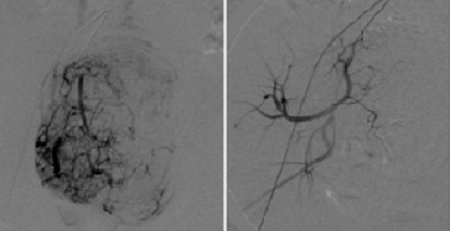

經(jīng)過周密的術(shù)前準(zhǔn)備,手術(shù)由放射科甄彥利主任和鐘小軍醫(yī)生共同實(shí)施,經(jīng)股動(dòng)脈引入一根直徑約1.6mm的導(dǎo)管,將導(dǎo)管分別插入雙側(cè)子宮動(dòng)脈,在DSA大型數(shù)字減影設(shè)備的監(jiān)視下,對(duì)瘤體進(jìn)行栓塞,將子宮肌瘤的血供斷掉,使瘤體逐漸萎縮。手術(shù)歷時(shí)約50分鐘順利完成。24小時(shí)后,馬女士已經(jīng)可以下床自由活動(dòng)了。

在DSA減影系統(tǒng)下可見,子宮肌瘤在經(jīng)過栓塞術(shù)后從10cm縮小到1cm